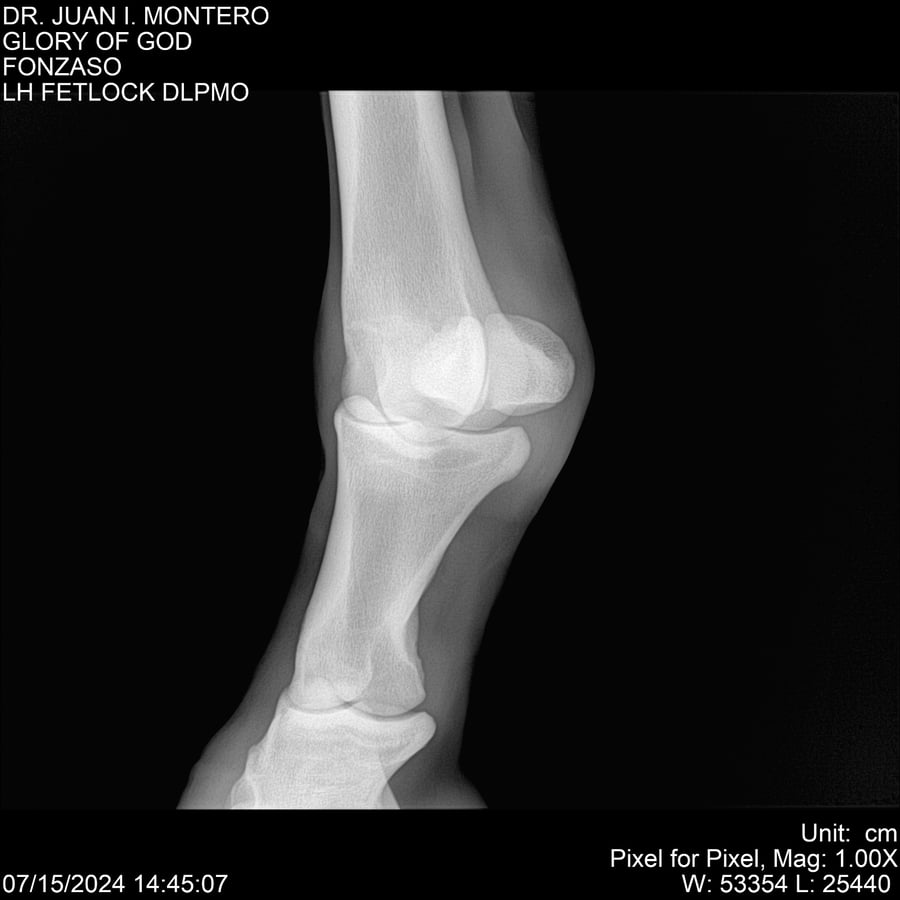

LOTE 10, GLORY OF GOD 🔥 🔥 🔥 Lote Anterior Volver al remate Lote Siguiente Ficha Contacto Montevideo - Ficha del Lote Identificador: #281389 Categoría: Yeguarizos Montevideo - 115 Visualizaciones ClicData Contacto Empresa: Abelenda N. R., Walter Hugo Nombre*: Teléfono* : E-mail* : Mensaje Enviar Registrese gratis Este contenido Exclusivo está disponible sólo para usuarios registrados Ingresar